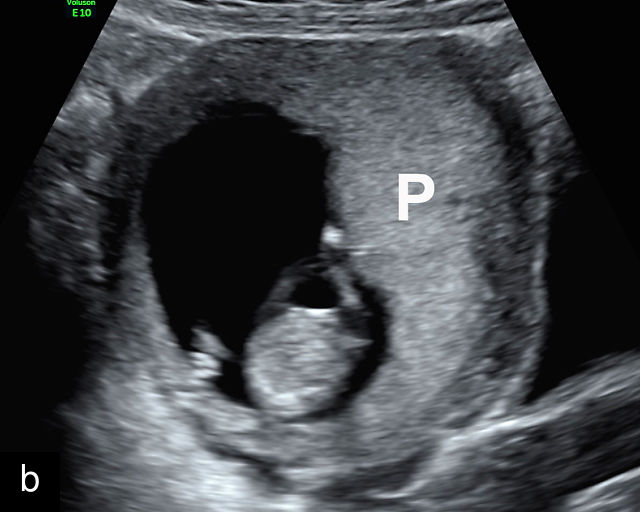

In the early first trimester, trophoblastic tissue appears as an echogenic ring encircling the gestational sac (Figure 1a). By the late first trimester, the placenta becomes recognizable as a distinct structure on ultrasound (Figure 1b). Initially, it presents as a homogeneous echogenic mass (Figure 1b–d) but undergoes progressive differentiation, becoming more heterogeneous as pregnancy advances from the second to third trimester (Figure 1e–g). By the third trimester, cotyledons become discernible, and in the late third trimester, calcifications frequently appear basally and around the cotyledons (Figure 1g).

1

Ultrasound images of development of the placenta (P/p). (a) Trophoblastic tissue appearing as an echogenic ring surrounding the gestational sac at 6 weeks' gestation. (b) Placenta at 12 weeks has become a discrete, uniformly echogenic mass. (c) Placenta at 17 weeks. (d) Placenta at 20 weeks. (e) Placenta at 27 weeks. (f) Placenta at 33 weeks. Increasingly, differentiation and heterogeneous appearance is seen, with demarcation of the cotyledons. Basal calcifications are beginning to appear. (g) Placenta at 40 weeks, showing a distinctly heterogeneous appearance, with clear demarcation of the cotyledons and presence of calcifications.